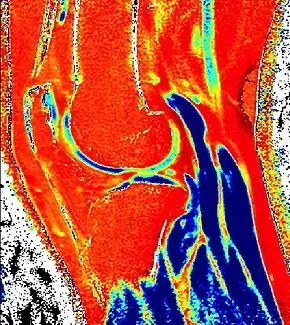

![]() dGEMRIC T1 Map of knee cartilage | |

Delayed gadolinium-enhanced magnetic resonance imaging of cartilage or dGEMRIC measures the fixed-charge density and relative proteoglycan content of articular cartilage using the spin-lattice relaxation time or T1 relaxation time.[1] Current research is investigating the clinical application of dGEMRIC as a quantitative tool for monitoring cartilage function in diseased or repair cartilage.[2]